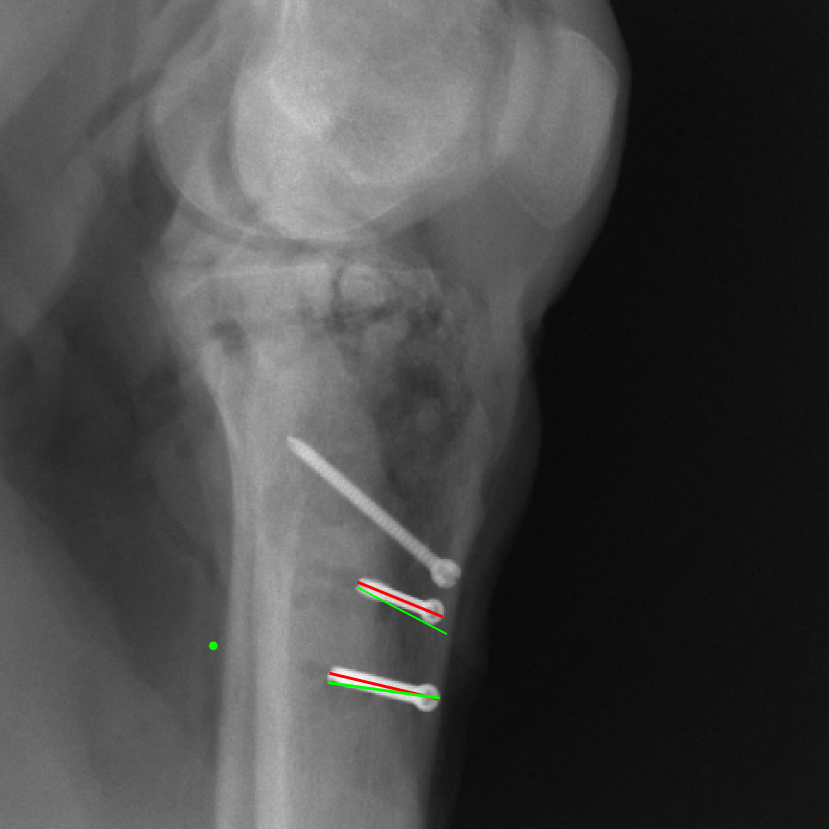

The complementary view setting for learning perspective deformation is also evaluated on real CBCT projection data. In this evaluation, real CBCT projection data from a dataset of knees with metal implants is used for testing, while DRRs created from volumetric CT datasets with inserted metals is used for training. Three exemplary DRR perspective projection images for training are displayed in Fig. 13, in which synthetic metal implants are inserted [34]. The appearance, e.g., image contrast and metal image resolution, of such DRR training images is different from that of real projection images in Fig. 14. In Fig. 14, the results for three knees, with and without metal implants, are displayed. The first and second rows are the 0superscript00^{\circ} and 180superscript180180^{\circ} perspective projections, respectively, rebinned to the virtual detector with geometric calibration based on their respective principal points and projections of the world origin. The third row displays their difference images, where the magnitude of deviation increases from the center towards the outside like it does in DRRs with an ideal scan trajectory (e.g., Fig. 6(e)), although real projection data suffer from various physical effects like beam hardening and Poisson noise. The fourth row displays the RGB stacks of 0superscript00^{\circ} and 180superscript180180^{\circ} perspective projection images. The magenta and green regions indicate structures with considerable perspective deformation, for example, the knee patella in Fig. 5.4, the top parts of the two metals in Fig. 5.4, and the bottom two screws in Fig. 5.4. The fifth row displays reference images, which are orthogonal projections of iterative reconstruction volumes from measured CBCT projection data. In the reference images, a total of five landmarks are selected, with the positions being marked by the green dots: In Fig. 5.4, two positions at the edges of the knee patella are marked; In Fig. 14(e) and Fig. 14(f), one position at the left edge of the fibula is marked for each image. In addition, a rectangular frame for the two metals is marked by the green dashed lines, while its width and height are indicated by the green solid lines, which are 29.71 mm and 111.99 mm, respectively. In Fig. 14(f), the centerlines of the bottom two screws are sketched by the green lines, which have the lengths of 17.14 mm (middle screw) and 19.38 mm (bottom screw). The corresponding rectangular frame for the two metals and the screw centerlines in the perspective projection images are marked as well, but in red color. In Fig. 14(a), the width and height of the metals are 32.56 mm and 109.85 mm, which have deviations of 2.84 mm and -1.95 mm to the reference ones, respectively. In Fig. 14(b), the centerline lengths are 18.91 mm and 19.54 mm, which have deviations of 1.77 mm and 0.16 mm, respectively. Although the bottom screw has little length deviation to the reference, the orientations of both screws are obviously deviated. The sixth row shows the results of Pix2pixGAN using 0superscript00^{\circ} and 180superscript180180^{\circ} polar inputs. For all of the landmarks, the green reference dots are all located accurately in the Pix2pixGAN images. The rectangular reference frame also accurately covers the metals in Fig. 14(g). In Fig. 14(h), although the two red centerlines do not exactly overlap with the green one, they are very close in lengths and orientations. Please zoom in for better visualization.

Figure 14: The results for the real cadaver leg data. The green dots mark the positions of landmarks in the corresponding reference images. In the first column, the arrows indicate the bone cavity/fracture structures. In the second column, the solid lines mark the widths and heights of the metals. The green ones are measured from the DRR reference, while the red ones are measured in the corresponding perspective projection image. In the last column, the lines mark the centerlines of the metal screws, where the green lines are those from the reference image. The lengths of the lines in mm are displayed in their corresponding subcaptions. Intensity window: [0, 4]. Please zoom in for better visualization.